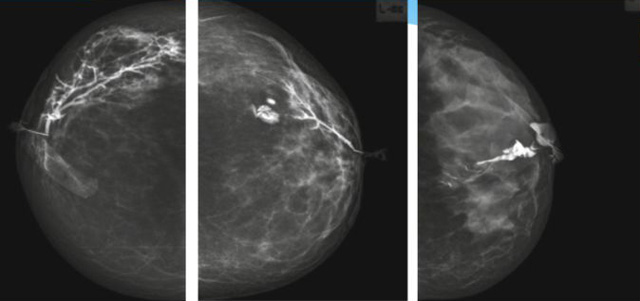

乳腺導管內乳頭狀瘤分為以下兩個,位于乳暈區(qū)大導管的中央型乳頭狀瘤,起源于末梢導管小葉單位的外周型乳頭狀瘤。外周型乳頭狀瘤常常沒有明顯的的臨床表現(xiàn),常因X線或乳腺超聲設備檢查發(fā)現(xiàn)。重點要關注的是中央型乳頭狀瘤,發(fā)生于任何年齡的女性,以40~50歲者居多。它表現(xiàn)為:單側乳頭溢液,特別是血性溢液少數(shù)病人可在乳暈區(qū)觸及腫塊。從病理學上面講表現(xiàn)為導管上皮和間質增生形成有纖維脈管束的乳頭狀結構。這是它一個病理學上的表現(xiàn)。它的超聲表現(xiàn)為:病變導管囊狀擴張呈無回聲,內可見乳頭狀低回聲或中等回聲。乳暈處的導管擴張,管腔內可見邊界清楚的,低回聲實性結節(jié)。外周型導管內乳頭狀瘤可,表現(xiàn)擴張為為低回聲的實性結節(jié),CDFI:部分腫瘤可顯示為軸心性的看到血流信號。乳腺增生癥:可見導管擴張,內無乳頭狀實性回聲,導管內乳頭狀癌:囊內乳頭狀癌病變較大,不規(guī)則,厚基底,血流豐富。以囊性為主的混合回聲,形態(tài)不規(guī)則,內見實性低回聲實性低回聲可見少量血流,病理為囊內乳頭狀癌。

乳腺超聲設備檢查的價值在哪里呢?它可以檢查發(fā)現(xiàn)乳暈周圍的各種病變,對于單側乳頭溢液、血性溢液的患者,超聲是首選的影像學檢查方法。注意:導管內乳頭狀瘤可合并不典型增生或,導管內乳頭狀癌,手術前懷疑時候,就應該手術切除而不是用微創(chuàng)手術。